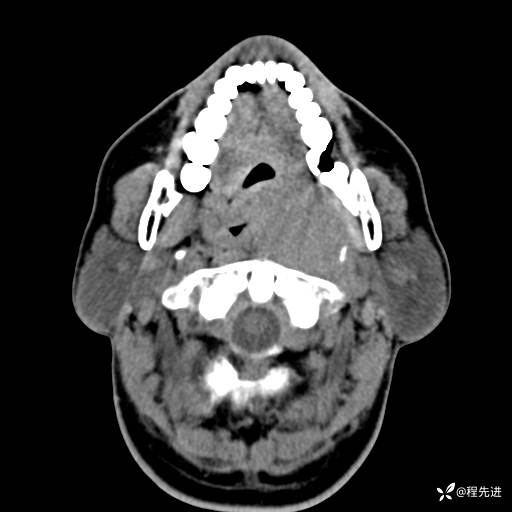

CT增强:

动脉期: